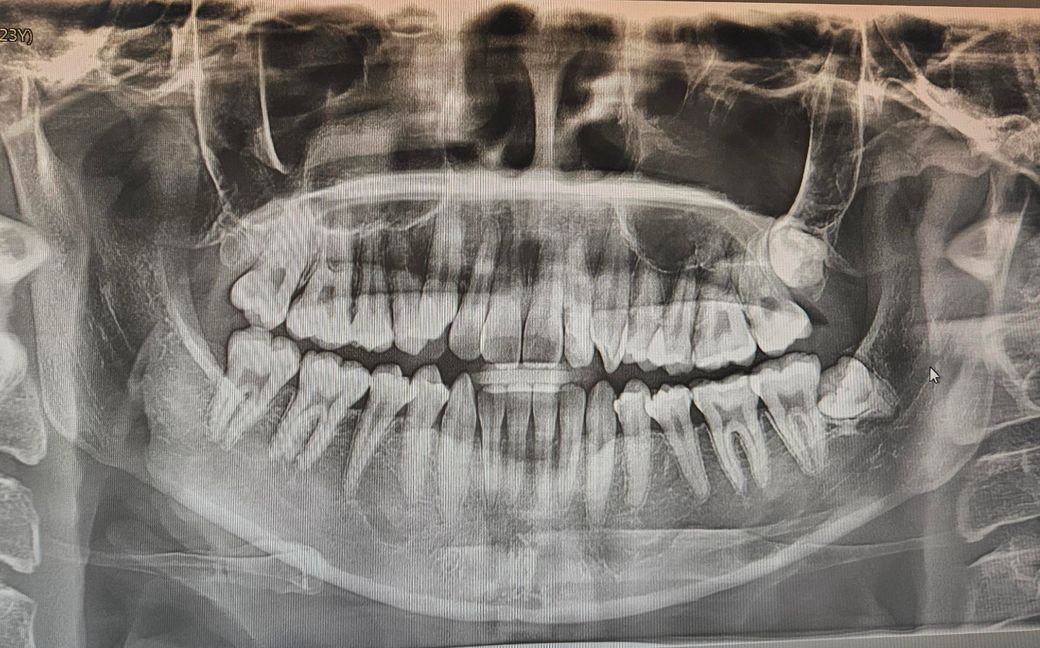

사진으로보이는 왼쪽 위 아래에 매복사랑니 질문인데요.

아래 매복사랑니는 뺄 수 있을 것 같은데. 위턱에난 사랑니도 뺄 수 있는 매복사랑니인가요? 저 정도로 위에 있는건 얼굴뼈 속에 난건가요?

저런 사랑니도 뺄 수 있나요...?

많이 위험할까요?

사랑니가 2개 잇는거 같습니다. 둘다 매복치료 같고 둘다 잇몸뼈에 뭍혀 잇는 상태입니다.

왼쪽 위의 사랑니는 깊이 매복되어 있습니다. 저 정도 깊이는 현재 꼭 필요하다면 뺄 수도 있지만 조금 기다리면 밑으로 내려올 수 있으니 더 기다렸다가 뽑는 것을 추천합니다. 위험한 것은 없지만 수술 범위가 커지니 일반적으로 뽑지 않고 기다립니다.

아래있는 사랑니는 발치해도 되지만 상악에 있는 사랑니는 굳이 무리하게 발치를 하지 안하도 될것으로 생각됩니다.

매복되어 있고 문제를 발생시키지 않는 사랑니의 경우 발치를 할 필요는 없습니다.

위쪽 매복 사랑니가 시야확보다 기구조작이 쉽지 않아 어려운 점들이 있지만 저정도라면 그렇게 어렵지는 않습니다. 너무 걱정하지는 않으셔도 되겠고 오히려 아래쪽 사랑니가 파노라마 상에서는 신경관과 조금 맞닿아있어서 발치후 신경손상 가능성에 대해 인지하고 계셔야겠습니다.